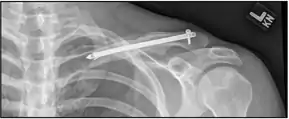

| X-ray of a left clavicle fracture | |

A discontinuity in the bone shape often results from a clavicular fracture, visible through the skin, if not treated with surgery. Surgical procedures often call for open reduction internal [plate] fixation where an anatomically shaped titanium or steel plate is affixed along the superior aspect of the bone by several screws. In some cases, the plate is removed after healing due to discomfort, to avoid tissue aggravation, osteolysis or subacromial impingement. This is especially important with a special type of fixation plate called hook plate.[14] With anatomical plates plate removal is considered an elective procedure that is rarely necessary. An alternative to plate fixation is elastic TEN intramedullary nailing. These devices are implanted within the clavicle's canal to support the bone from the inside. Typical surgical complications are infection, neurological symptoms distal the incision (sometimes to the extremity), and nonunion of the bone (failure of the bone to properly fuse together).